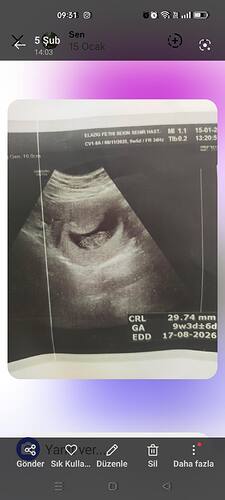

Çok net değil ama duruş kız bebek gibi canım daha net bir fotoğraf var ise paylaşabilirsin

Çok net değil ama kese kız kesesi gibi net fotoğraflari olunca tekrar atarsın cnm

Erkek bebek canım ama biraz daha gelişine tekrar at